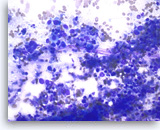

Pancreatic endocrine neoplasm #1,

Pancreas FNA, Direct Smear.

The aspirates show single and dyshesive clusters of neoplastic cells. The neoplastic cells show mild variation in size and have eccentrically located oval nuclei (plasmacytoid appearance). A few small cytoplasmic vacuoles are seen.

40X